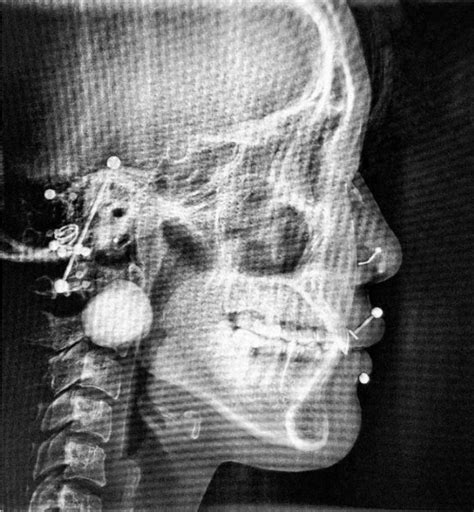

Multiple Facial Piercings, X Ray

The simple answer is that body jewelry appears as a solid shape on your x-ray. While this isn't inherently bad, the black or white blob that appears on your x-ray can actually obscure important medical information. If you have a piece of metal jewelry in your piercing, it might cover up something important. A nose ring may get in the way of a clear view of your sinuses, whereas tongue piercings may block information related to your mouth or jaw.

This individual also has several ear cartilage piercings. On the left, it looks like they may have a daith and a tragus piercing. On the right, it looks like it may be a conch and a helix piercing.